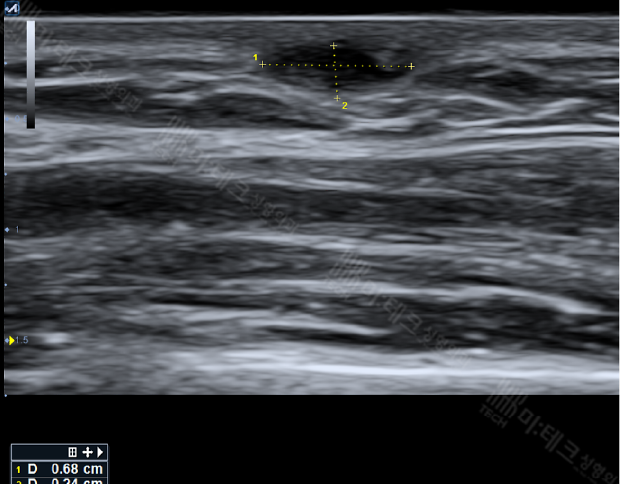

- 약 0.7cm가량의 저음영의 에코가 표면에 보입니다.

경계가 명확지 않고 아래로 그림자가 짙지 않습니다.